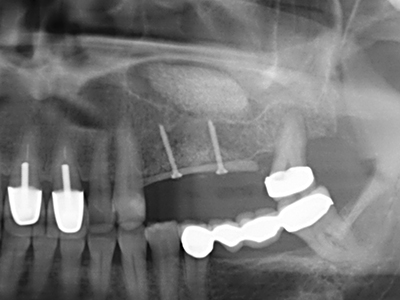

Fig. 11: la panoramica postoperatoria mostra l'accrescimento verticale e il rialzo del pavimento sinusale.

Fig. 15: la radiografia dopo un follow up di un anno mostra condizioni stabili a livello osseo.